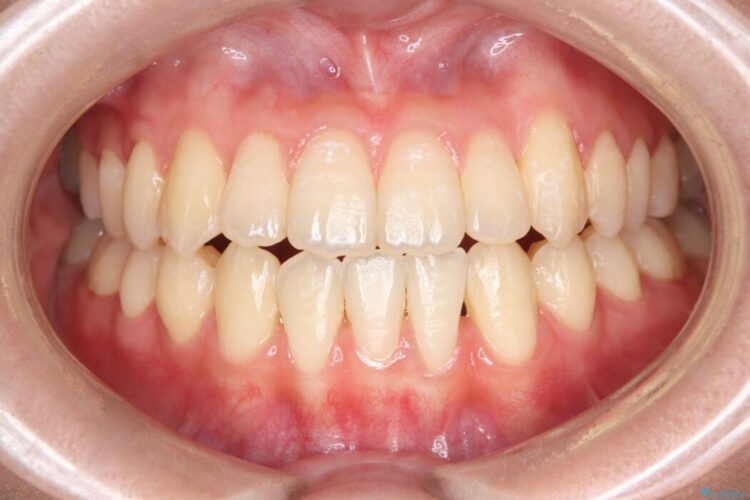

長期的な安定性を重視したセラミック治療

歯と歯の間に虫歯があった患者様です。

治療期間(治療回数):1ヶ月(2~5回) | 概算治療費:13.2万円(税込)(仮歯:10,000円+オールセラミッククラウン 3年保証110,000円)